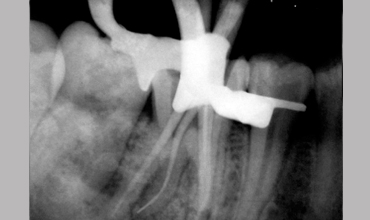

Management Of Radix Entomolaris In Mandibular First Molar